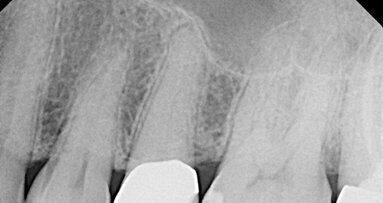

The patient pictured in Figure 1 was referred because the first clinician could not locate the canal(s). The patient had pain when chewing on #13 and mild ...